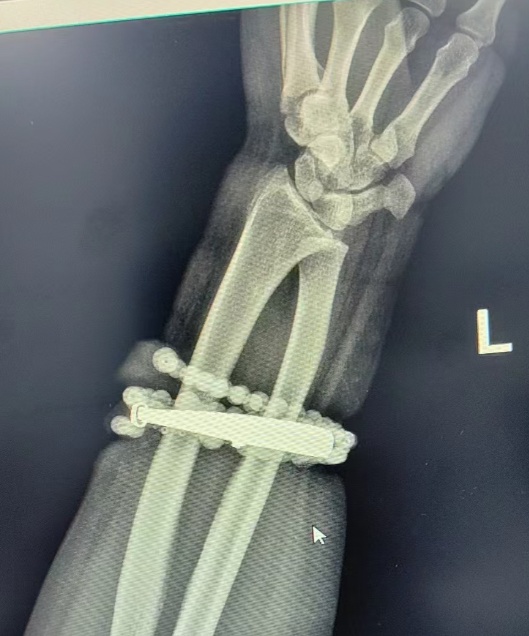

医生对女子手部进行检查。图源:央视网